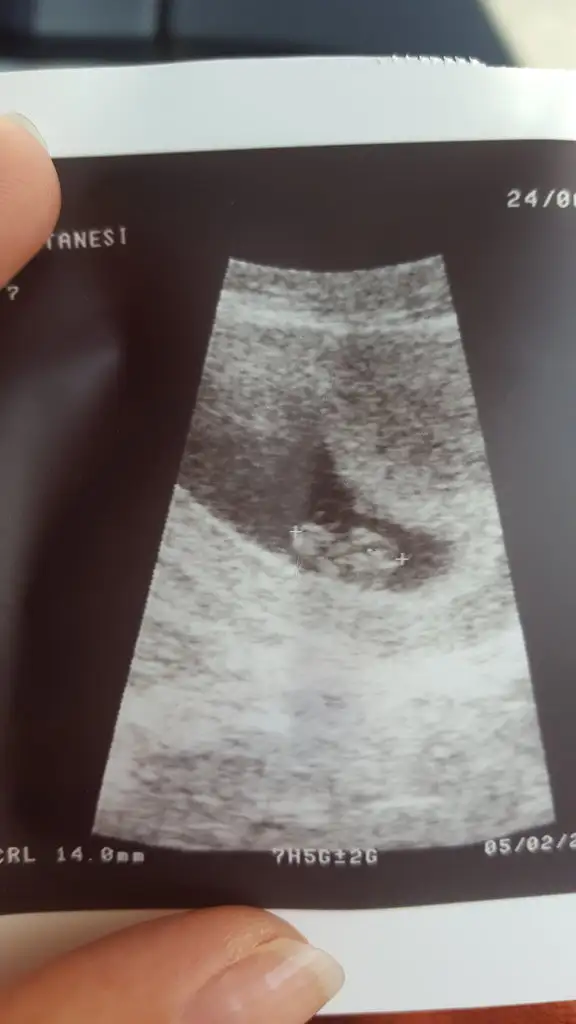

Doktora görünün isterseniz kanamanız varmış. Ne olur ne olmaz diye düşünüyorumArkadaşlar yardım ederseniz sevinirim. Benim sat 21 Mayıs, beklediğim adet günüm 2 gun geçince idrarda pozitif, kanda 302.10 çıktı. Doktor keseyi adet gecikmesinin10.gunu görebildi ve ultrasona göre 4+6 ama kendi fikrine göre 3 haftalik olduğunu söyledi. Benim dünden beri kahverengi lekelenme ve birazda hafif sancilarim var. Sizce yerlesme kanamasi mıdır yoksa doktora gideyim mi? Birde 3 haftalıksa eğer ben testleri 2. Haftada yapmış oluyorum. 2. Haftada idrarda net pozitif, kanda 302 cikarmi sizce